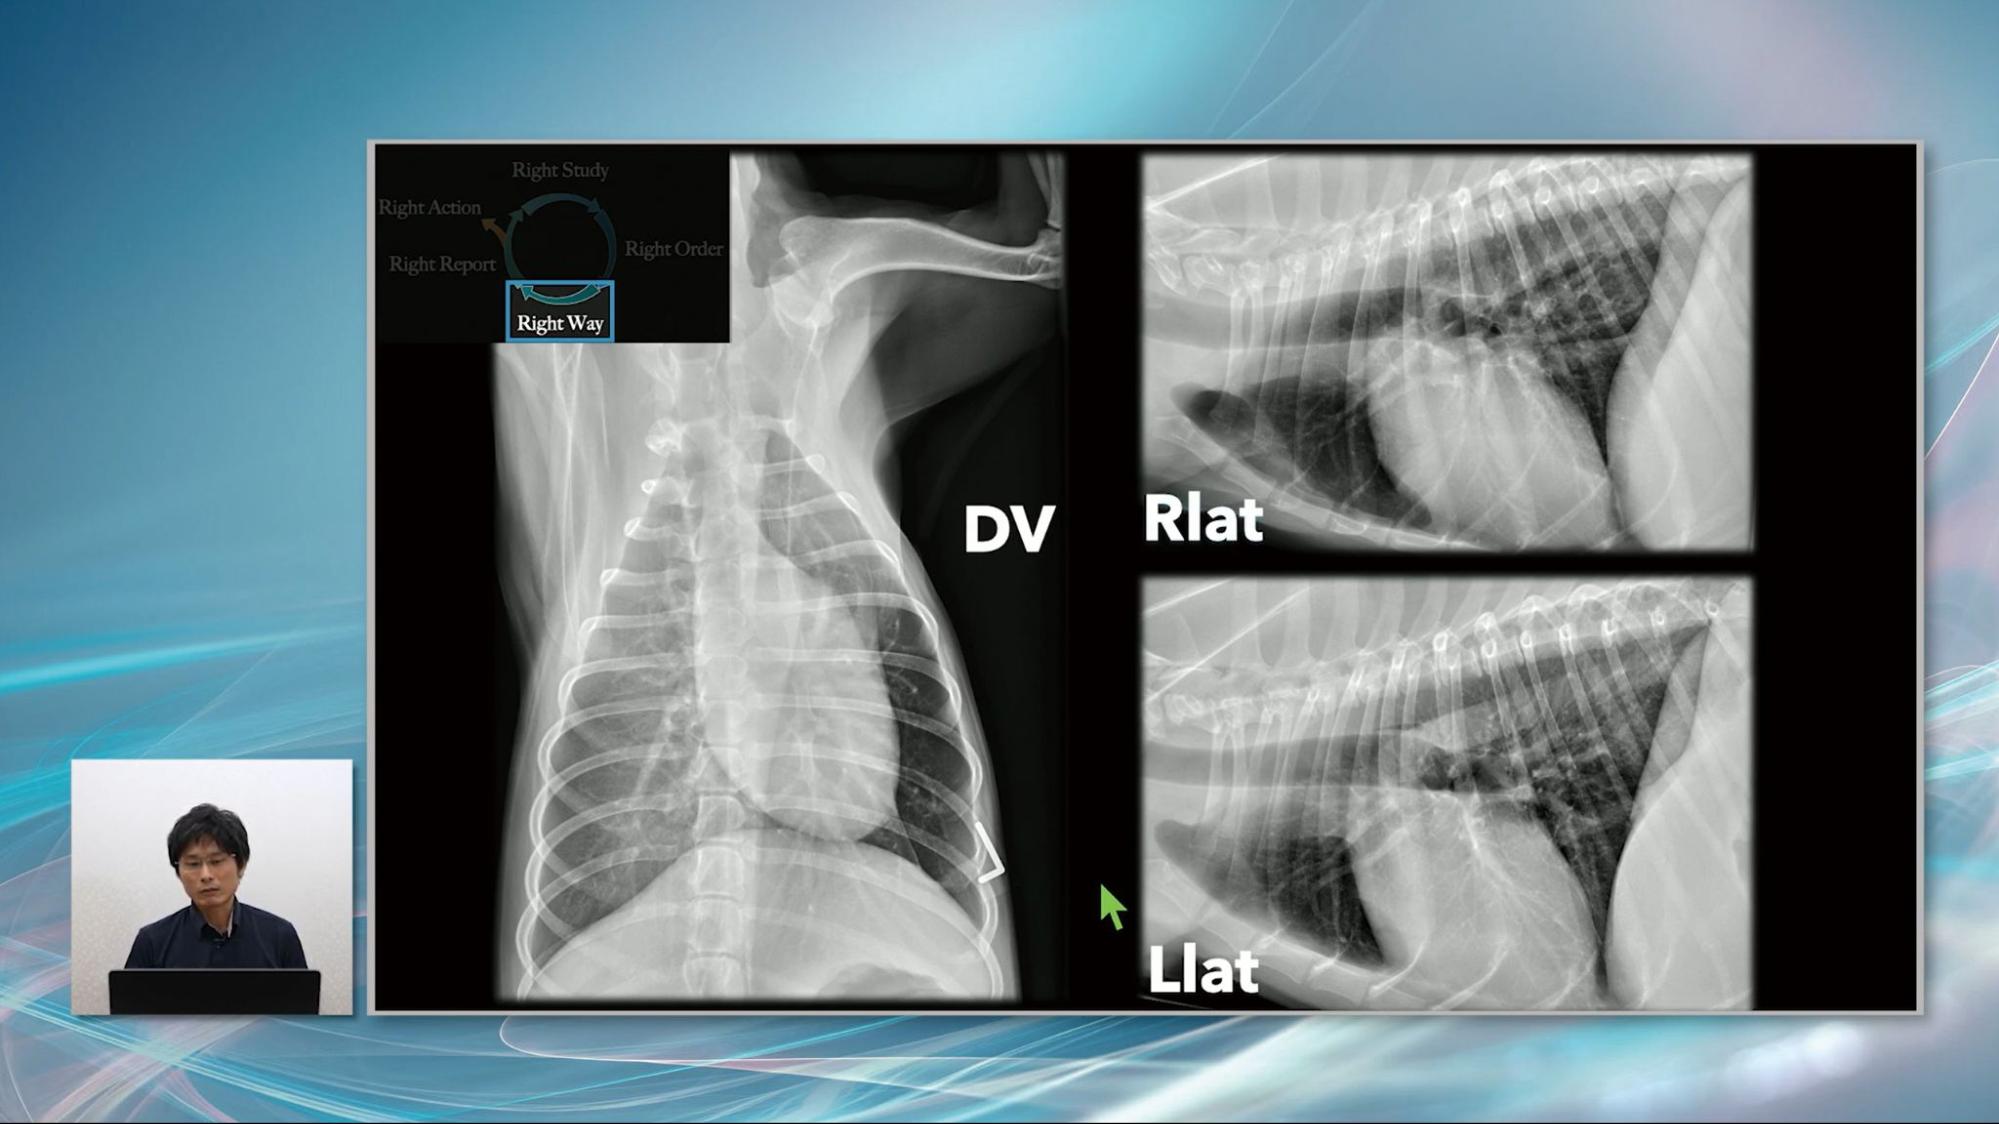

2冊セットです①犬と猫のX線検査著:堀 あい監修:中出 哲也B5判 144頁 オールカラー2020年6月発行定価:本体5,800円(税別)②犬と猫の超音波検査著:華園 究監修:中出 哲也B5判 144頁 オールカラー2020年3月発行定価:本体6,800円(税別)- 出版社: 緑書房値下げ不可、即購入可です。購入後ほとんど読まずに保管していた美品です裁断なし、書き込みや折れはありません。あくまで素人保管のため中古品にご理解ある方ご購入よろしくお願いします。